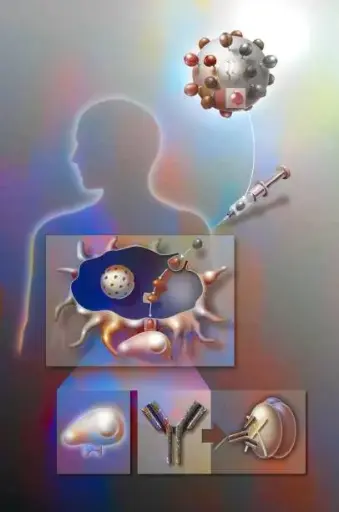

This course offers a comprehensive exploration of immuno-oncology, bridging foundational immunological principles with cutting-edge cancer immunotherapies. Designed for healthcare professionals, researchers, and advanced students, Immuno-Oncology Unlocked delves into the cellular and molecular mechanisms that drive immune responses against cancer, including antigen recognition, immune surveillance, and tumor immune evasion. Participants will gain in-depth knowledge of therapeutic strategies such as immune checkpoint inhibitors, CAR-T cell therapies, cancer vaccines, and tumor-infiltrating lymphocyte (TIL) therapy. The course also addresses key topics in clinical application, including biomarkers for patient selection, immune-related adverse events, and the integration of immunotherapy into standard oncology care. Through case studies, current clinical trial data, and expert-led discussions, learners will be equipped to critically evaluate and apply the latest advancements in the rapidly evolving field of cancer immunotherapy.